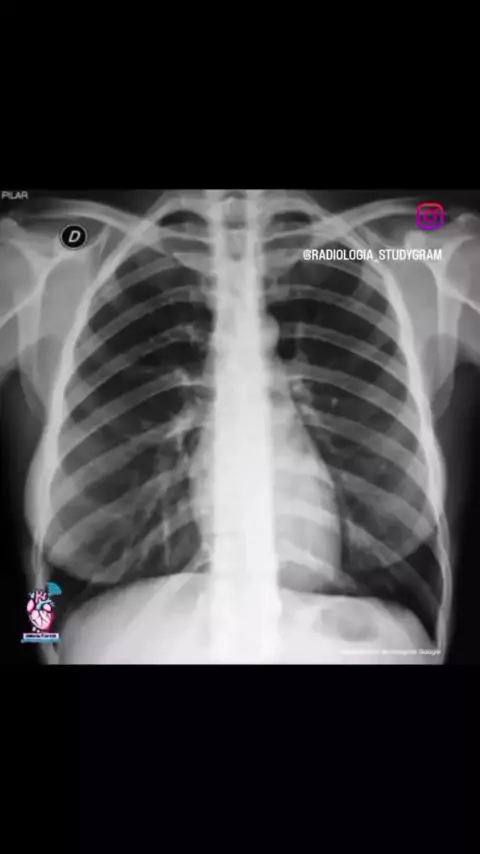

#torax